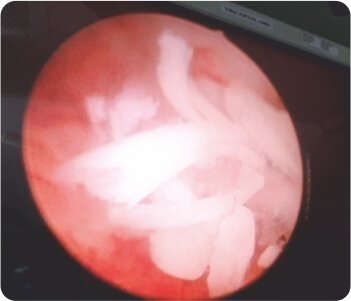

Hysteroscopic pics of retained fetal bones in the uterine myometrium